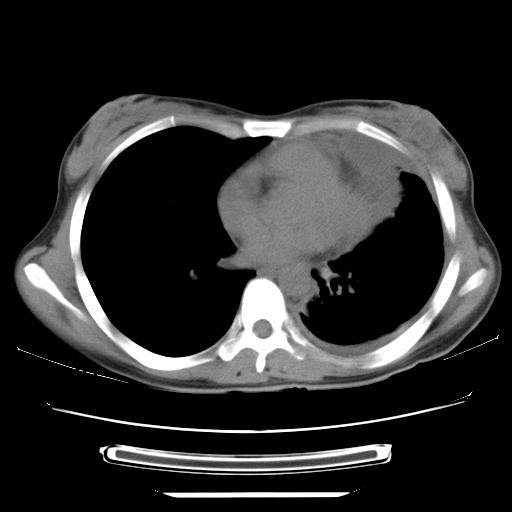

标题: CT21561:外院胸片提示胸腔积液,行CT检查。 [打印本页]

女,29岁,胸部不适,在外院胸片提示胸腔积液,到我院ct检查。

纵膈窗

1、左侧包裹性积液伴叶间积液 2、右肺多发结节考虑增殖结节

左侧纵隔胸膜包裹性积液、左侧胸腔积液、胸膜肥厚粘莲,考虑结核性胸膜炎

左肺上叶不张,左侧胸水,叶间裂积液,纵隔淋巴结,脾脏钙化,考虑左肺上叶支气管内膜结核,结核性胸膜炎,脾结核

考虑:1.两肺tb;2.左侧胸膜炎、胸腔积液。

考虑两肺结核,左侧包裹性积液,叶间积液。

支持两肺继发性肺结核,左侧胸膜腔包裹性积液、胸膜肥厚,脾内多发钙化(结核钙化)。

右肺多发结节。左胸腔多发包裹性积液。